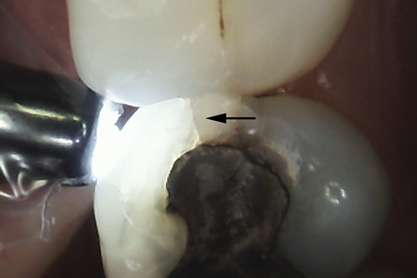

Whenever asymptomatic enamel cracks extend into dentin and cannot be eliminated by minimally invasive fissurotomy without causing additional damage to the tooth and underlying structures, protection is recommended to minimize their propagation (Figure 10 and Figure 11).3,14 Occlusal coverage restorations have demonstrated greater overall success in the treatment of symptomatic cracks by immobilizing the cracked segments that move on loading, with better prognosis seen when more conservative restorations are used.27,28 Although this might still be controversial, from a biomechanical perspective these principles can conceptually apply to the treatment of asymptomatic dentin cracks. Occlusal coverage restorations have been recommended to protect asymptomatic teeth with existing dentin cracks from further cracking (Figure 12).2,3,9,29

Fig 10. Stained asymptomatic enamel marginal ridge crack (arrows) of a maxillary right first molar extending to the existing restoration (mesio-occlusal view).

Figure 10

Fig 11. Exploratory fissurotomy and methylene blue dye staining revealing an underlying deep dentin crack in the tooth shown in Fig 10.

Figure 11